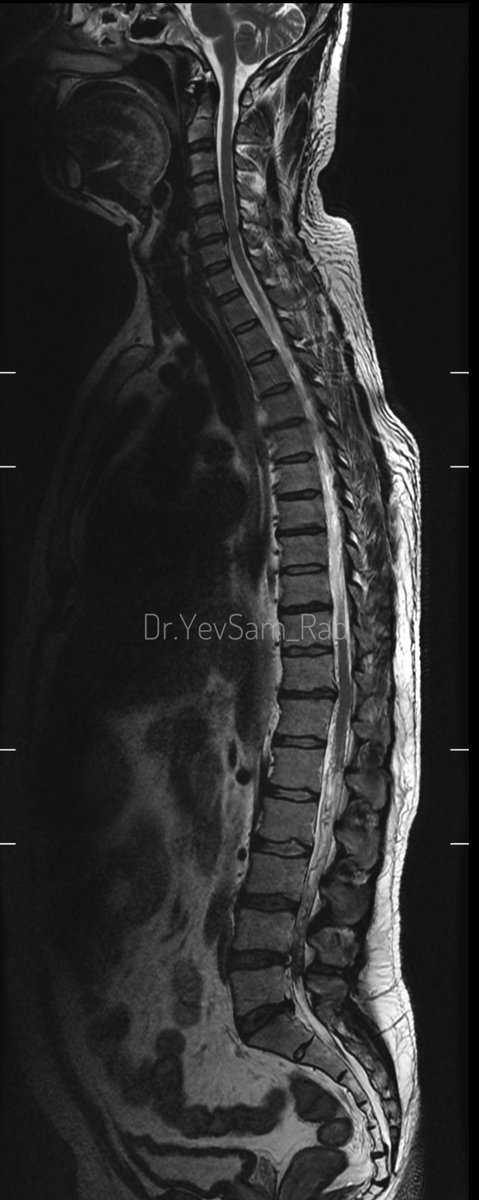

Young gentleman came with severe low back ache following an episode of dengue fever. What do we see here? #spineimaging #medtwitter #radtwitter #FOAMrad #neuroimaging @drvenkimdrd